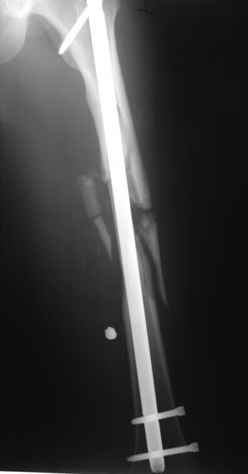

В нашем случае 21 летний боец уличного фронта, фиксацию провели на следующий день, зафиксирован интрамедуллярным штифтом. Не стали делать первичную хирургическую обработку точечной раны, зафиксирован как есть. Клинические снимки:

Конечно, наш случай не эталон, возможно, на месте вам виднее, может быть, нет необходимости ориентироваться на зарубежные ссылки, если получается лечить аппаратом Илизарова на месте, почему нет? Необходимо посмотреть собственный арсенал, чем фиксировать, и какая теория, иначе любой отличный метод можно превратить в источник остеомиелита.